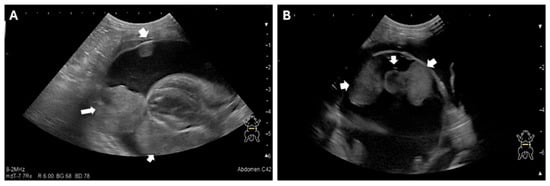

2.2. Referral and Diagnostic Evaluation